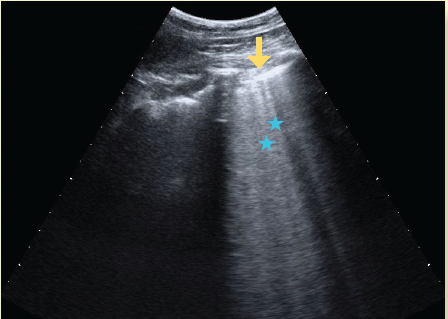

El ultrasonido es un método seguro, transportable a la cama del paciente, libre de radiación ionizante y de bajo costo, por lo que es útil en el diagnóstico y monitoreo de pacientes con infección por SARS-CoV-218. El hallazgo principal en ultrasonido es la enfermedad intersticial aguda, que produce artefactos hiperecoicos verticales que se apartan de la línea pleural, llamadas líneas B. El pulmón que pierde su contenido aéreo progresa de presentar un patrón pulmonar normal (con líneas A, las cuales se caracterizan por ser horizontales, cortas e hiperecoicas) a observar líneas B no coalescentes, después líneas B coalescentes hasta llegar a la consolidación19-21 (figuras 5a, 5b, 5c, 5d).

Figura 5b Ultrasonido en escala de grises del tórax, donde se observa la línea pleural (flecha amarilla) y las líneas B (estrellas azules), estas últimas traducen engrosamiento intersticial